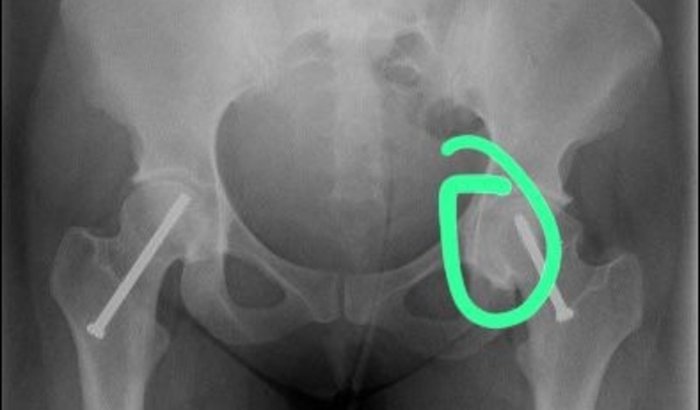

Olá. Me chamo Bruna e coloquei um pino há 16 anos atrás. Hoje com 27 depois se sentir dores, fui no hospital e com o raio x decretou um desgataste no fêmur. O médico me passou uma medicação para ajudar a desgastar menos, se não será necessário colocar uma prótese de cerâmica. Quem puder me ajudar com 5 reais, já vai ajudar muito.